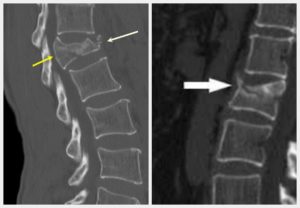

Степени компрессии переломов позвонков нельзя определить только при осмотре. Требуется обязательное проведение рентгенологического обследования. Снимок делают минимум в двух проекциях.

Определяют высоту поврежденного позвонка и процентное соотношение с высотой здорового. Также рентген позволяет провести дифференциальную диагностику первой степени компрессионного перелома позвоночника и вывиха или растяжения связок.

С помощью рентгена или томографии определяют степень перелома

Компрессионный 3 степени перелом тела L1 позвонка